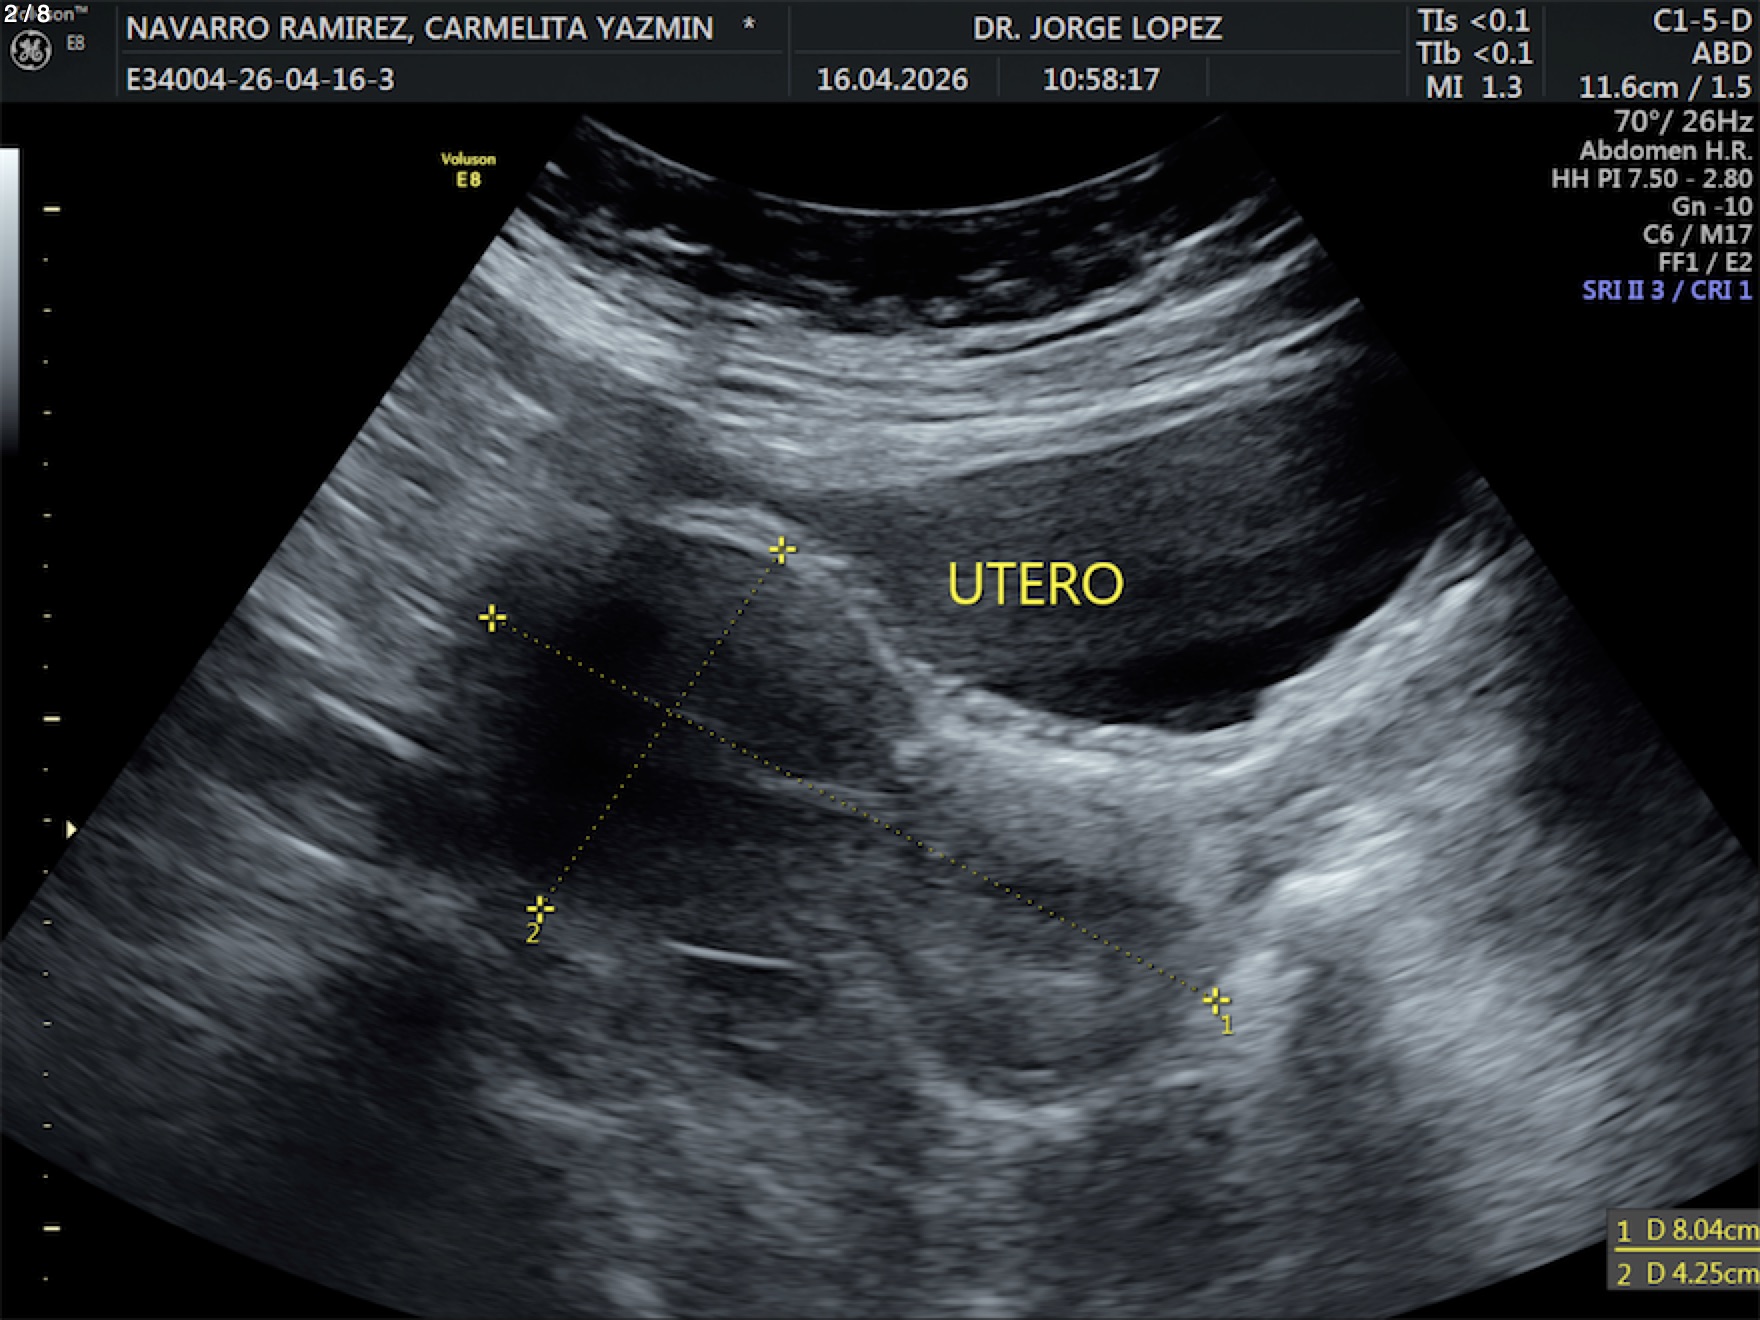

Navarro Ramirez Carmelita Yazmin - Unnamed